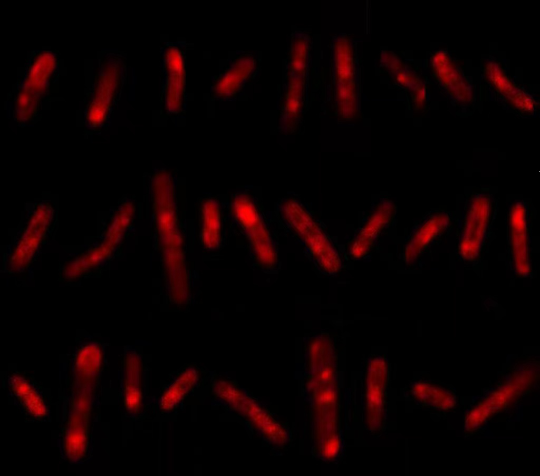

周泱介绍:“这个探针能够特异性地‘咬’住结核分枝杆菌的糖蛋白,同时它还带有一条‘尾巴’,如果糖蛋白是活性的,就代表这个结核分枝杆菌是活的,探针的‘尾巴’就会亮起荧光,灵敏度非常高。”

通过这种检测方法,医护人员在华女士的血液和尿液标本里找到了大量活的结核分枝杆菌,结合肾脏功能指标,她被确诊为肾结核,接受了为期6个月的抗结核治疗。从治疗起,华女士的症状就逐渐消失,肾脏功能指标也在好转。

华女士的检测结果 亮起荧光代表有活的结核分枝杆菌